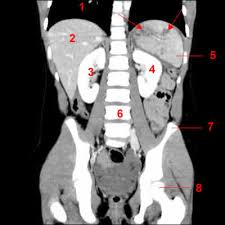

Tomodensitrométrie

La tomodensitométrie (TDM), dite aussi scanographie, tomographie axiale calculée par ordinateur (TACO), CT-scan (CT = Computed Tomography), CAT-scan (CAT = Computer Assisted Tomography), ou simplement scanner pour l'appareil[1], est une technique d'imagerie médicale qui consiste à mesurer l'absorption des rayons X par les tissus puis, par traitement informatique, à numériser et enfin reconstruire des images 2D ou 3D des structures anatomiques. Pour acquérir les données, on emploie la technique d'analyse tomographique ou "par coupes", en soumettant le patient au balayage d'un faisceau de rayons X.